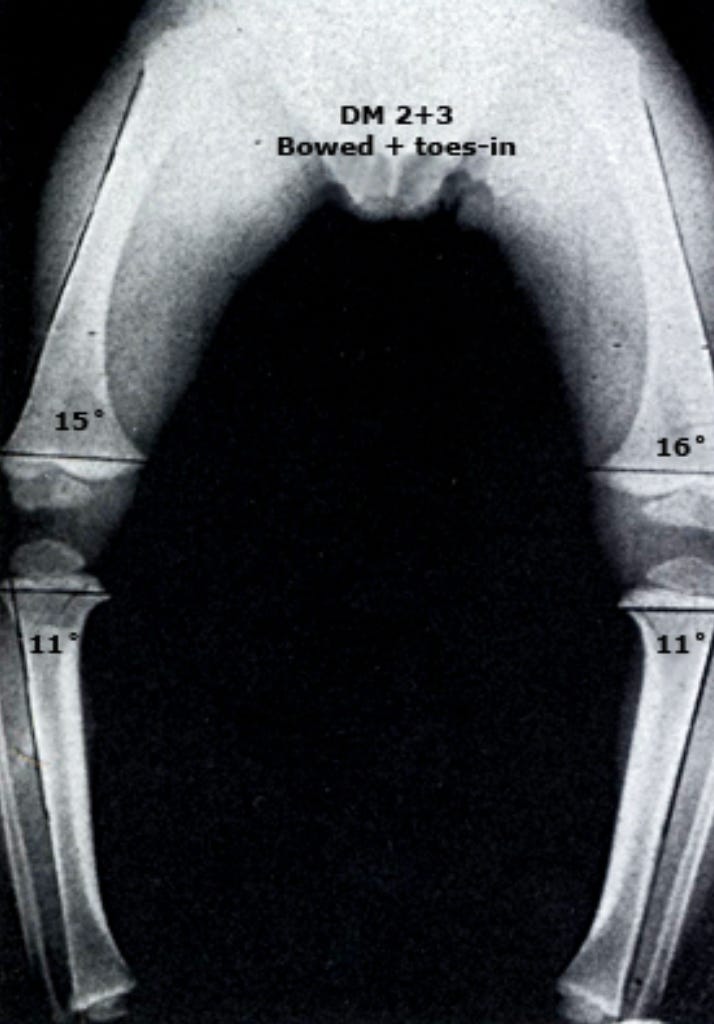

Рентгенологические особенности (при выполнении):

Метафизарно-диафизарный (МД) угол большеберцовой кости: <11°

Соотношение МД углов: бедренный МД угол больше большеберцового МД угла (отношение >1)

МД угол большеберцовой кости >16° (хотя этот признак не является диагностическим)

Соотношение МД углов бедро:голень <1

Угол между метадиафизарный угол измеряется на переднезаднем рентгеновском снимке коленного сустава в положении стоя следующим образом: 1) проводится линия вдоль продольной оси большеберцовой кости (линия 1); 2) проводится линия через вершины проксимального метафиза большеберцовой кости (линия 2); 3) проводится линия, перпендикулярная линии 1, в точке пересечения линий 1 и 2 (линия 3); 4) измеряется угол между линиями 2 и 3 — это и есть угол между метафизом и диафизом большеберцовой кости. Значение угла ≤11° указывает на физиологическую, а не патологическую О-образную деформацию. У этого пациента с болезнью Блаунта метадиафизарный угол равен примерно 18°.

Метафизарно-диафизарные (МД) углы:

Цель: определение локализации и относительной тяжести деформации

Техника измерения: угол между линией, проведенной через метафиз, и линией, проведенной через диафиз кости

Большеберцовый МД угол >16°: предполагает болезнь Блаунта

Соотношение бедренный МД угол : большеберцовый МД угол:

>1: предполагает физиологическое искривление

<1: предполагает болезнь Блаунта